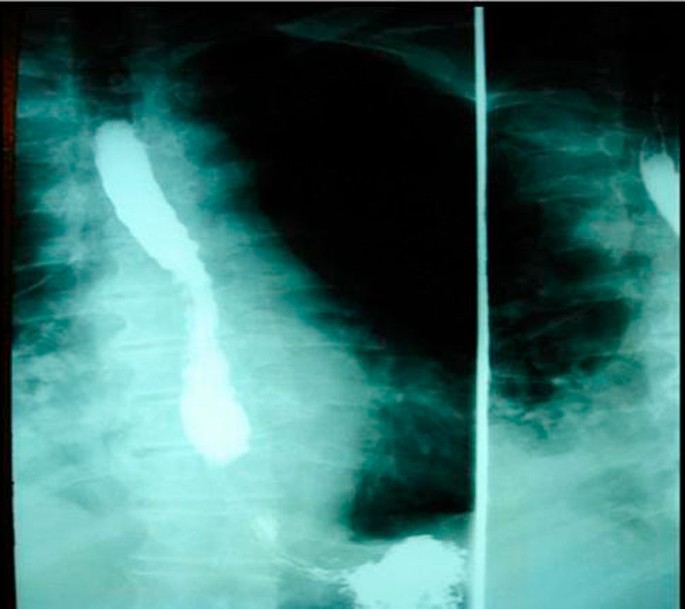

A subsequent hypaque swallow study failed to demonstrate extravasation of contrast medium (Figure 2). Erect chest x-ray a few hours later demonstrated contrast medium extravasation accompanied with large pleural effusion (Figure 3). Subsequent CT scan demonstrated right sided pneumothorax, extended right sided pleural effusion and a small amount of air in the mediastinum (Figure 4).